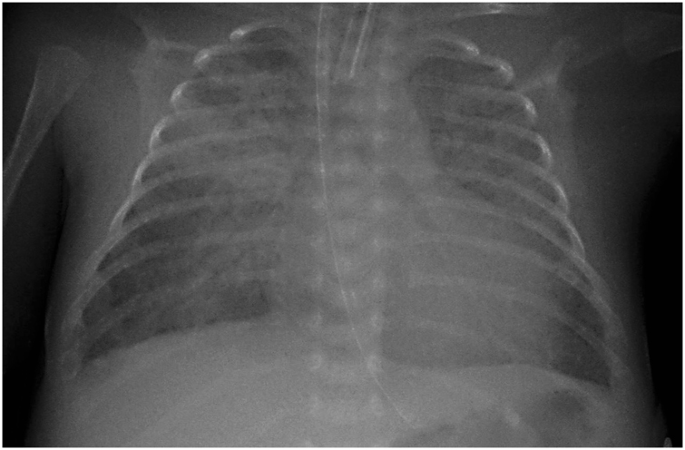

International Expert Consensus Statement On Chest Imaging In Pediatric Covid 19 Patient Management Imaging Findings Imaging Study Reporting And Imaging Study Recommendations Radiology Cardiothoracic Imaging